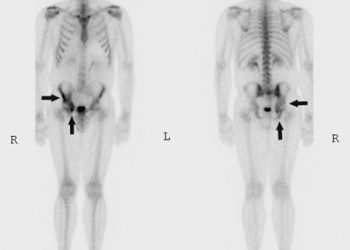

Metastaze osoase

Sistemul osos este cea mai frecventa localizare a metastazelor. Determinarile secundare osoase apar cel mai adesea în cadrul unui cancer de prostata la barbati, cancer de sân la femeie sau cancer pulmonar (la ambele sexe).

Metastazele osoase sunt de obicei multiple și se grefează cu predilecție la nivelul scheletului axial. Majoritatea metastazelor (90%) se dezvoltă în vertebre, pelvis, femur/humerus proximal, coaste, stern, oasele bazinului sau craniu. Există și o serie de asocieri particulare ale anumitor forme de cancer cu localizarea metastazelor osoase: de exemplu, 50% din metastazele la nivelul mâinii au ca punct de plecare un cancer pulmonar, iar tumorile din pelvis dau adesea determinări secundare în bazin și coloana lombosacrată.

• imagistică – pentru diagnostic, planificarea tratamentului și urmărirea metastazelor osoase. Scintigrafia whole-body cu Tc-99m este cea mai bună metodă de screening pentru prezența determinărilor secundare osoase. Ulterior, metastazele pot fi bine caracterizate prin radiologie convențională, CT, IRM sat PET-CT.